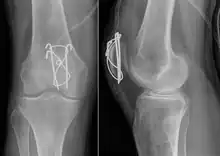

Comminuted fracture of patella

Surgery

Most patella fractures are transverse or comminuted, hence the quadriceps mechanism is disrupted and they are treated by a combination of wires in a tension band construct. This unites the fractured bones, reconstructing the straightening mechanism of the leg.[5][6]

If the patella is broken in several places, that is comminuted, then traditionally a patellectomy (removal of the whole patella) is performed in order to reconstruct the extensor mechanism and prevent the onset of an extension lag at the knee joint, resulting in instability.[5][10][11] Some surgeons however would rather opt for internal fixation.[10] A partial patellectomy is removal of only a portion of the patella, and may be carried out if at least 60% of the patella can be maintained.[10][6]